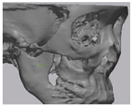

2.2. Computer-Aided Virtual Surgery, Design, and Fabrication of Patient-Specific Devices

2.5. Cone Beam CT and 3D Comparison

3.2. Fusion Rate Analysis Using 3D CT

3.3. 3D Comparison between Immediate Post Operative and 6 Months Post Operative